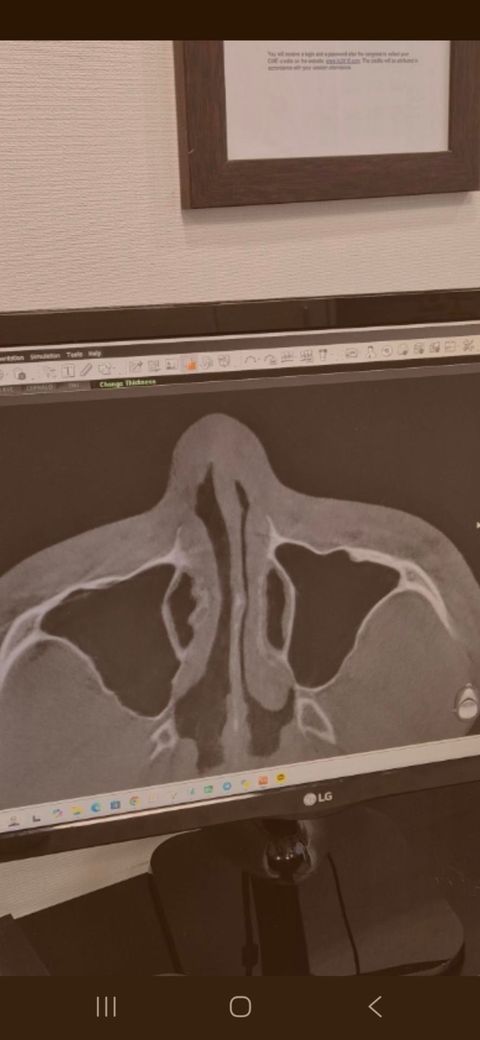

• 2번 째 사진

CT 단면 사진으로만 봤을 때에는 약간의 비중격 만곡증이 있는 것으로

보이는데 이것이 정면 사진도 같이 확인이 필요한 것으로 보이며 만곡증의

정도가 심하지는 않아 재 수술이 필요하지는 않을 것으로 보입니다.

걱정이 많이 되시겠습니다만, 두개의 영상 사진이 전혀 다르며, 저 CT와 엑스레이만으로 평가하는 것도 아닙니다. 궁금하시면 수술하셨던 병원 가셔서 재진 보시면 되겠습니다.

비중격만곡에 대한 교정 수술을 하더라도 비중격의 좌우 대칭이 완전히 일치하지는 않습니다. 비중격만곡 교정술을 시행한 것으로 보이는 흔적이 관찰되며 상기 소견으로 보아 비중격만곡증이 다시 재발했다고 보기는 어렵습니다. 답변이 도움이 되었기를 바랍니다.